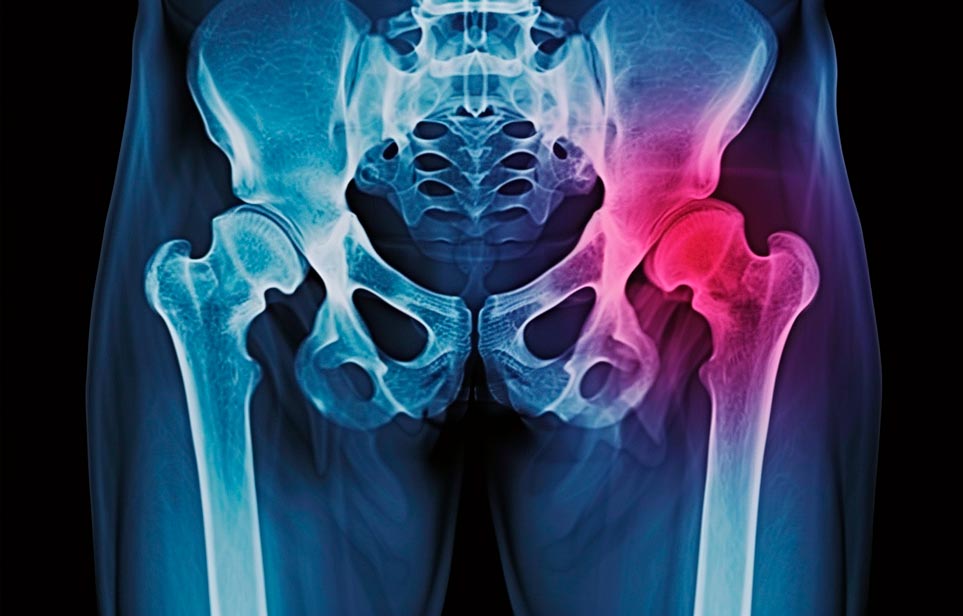

Реабилитация пожилых после перелома шейки бедра в Балаково

Такая травма в большей части случаев возникает у граждан преклонного возраста. При её появлении на протяжении длительного времени сохраняются болевые и неприятные ощущения в области паха, при которых серьёзно ухудшается качество жизни, возникает множество последствий для его жизни и здоровья.

По какой симптоматике можно определить перелом шейки бедра?

- Визуально повреждённая нога сокращается на несколько сантиметром из-за сокращения мышц.

- Стопа выворачивается наружу.

- В лежачем положении человек не может поднять ногу.

При такой симптоматике важно незамедлительно обращаться к специалистам для получения всей необходимой помощи, терапии и восстановления после перелома шейки бедра. Если не оказать помощи старику, то это приведёт к гноению, инвалидности, иным видам осложнений.